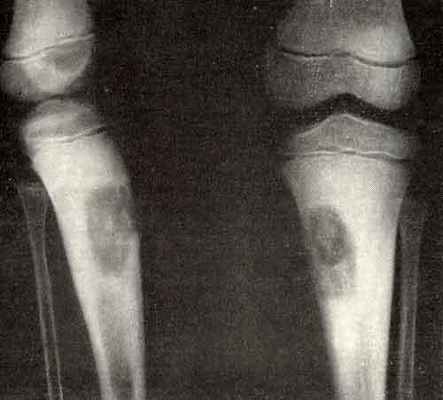

Неостеогенные опухоли образуются в бедренной кости и провоцируют разрушение трубчатых костей скелета. В запущенной стадии заболевание становится причиной патологического перелома кости. Редко (3–5% клинически диагностируемых случаев) новообразование уменьшается в размерах без хирургического вмешательства. Другие виды костных опухолей отличаются агрессивным ростом. Так, десмопластическая фиброма способна увеличиться в объеме вдвое за 2–3 недели.